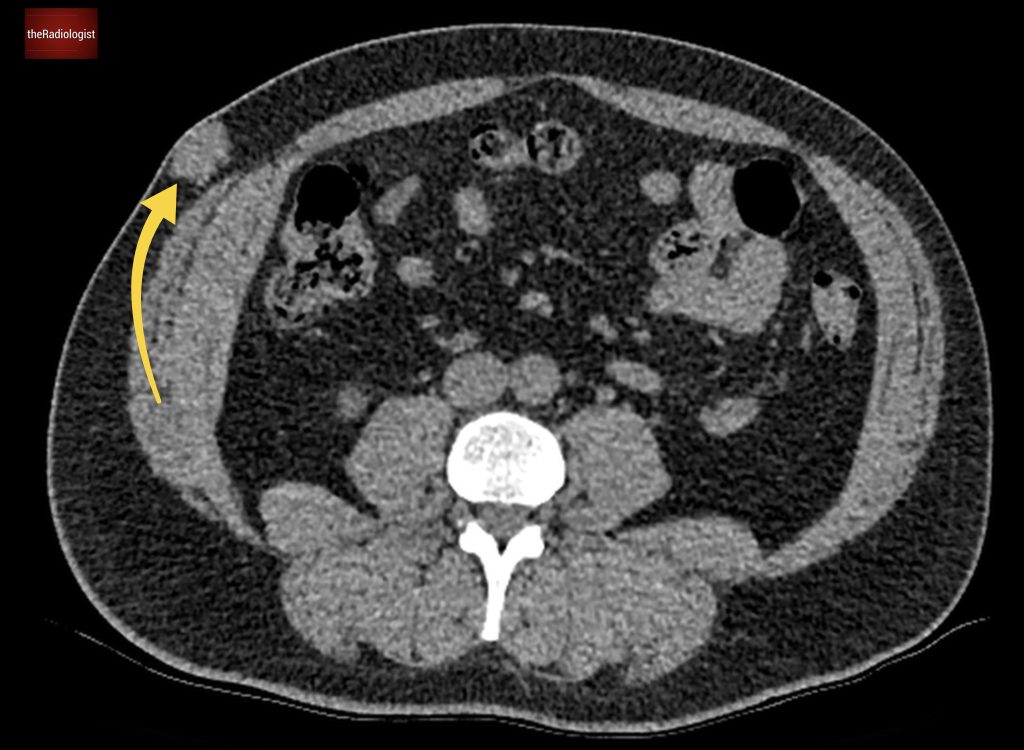

If we look at the psoas muscles on this scan below we can see there is some asymmetry . The right psoas is larger than the left and we’ve lost some of the fat planes within the muscle.

Compare the psoas muscles side by side. The right sided psoas muscle appears expanded with a loss of its normal fat planes.

Also as we scroll down we can see there is fat stranding surrounding the psoas muscle extending into the pelvis.

There is fat stranding surrounding the psoas extending into the pelvis.